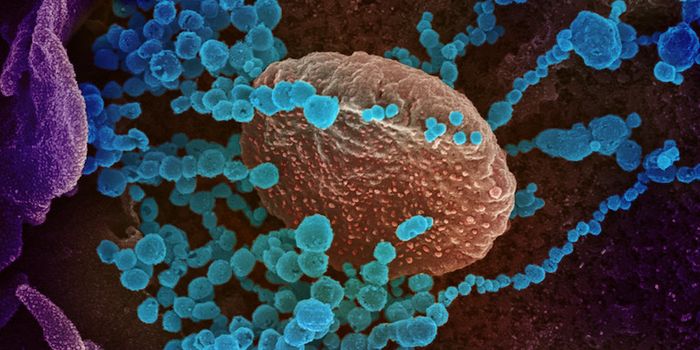

APR 24, 2022ImmunologyA variety of studies by different reseaech groups have now confirmed that the Pfizer-BioNTech mRNA COVID-19 vaccine is s ...